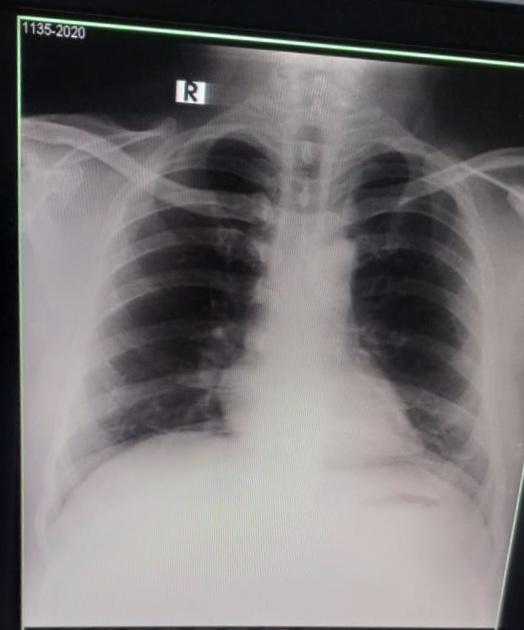

My brother is covid positive. He is diabetic too. He is having sore throat and body ache now. The attached photo is his chest X-ray. Can you please tell what’s his state now.

Chest d rat show inflamation in lungs consult online for detailed assessment